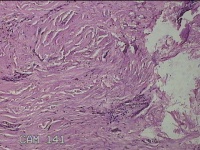

右下腹部切口结节

性别

女

年龄

27岁

临床诊断

皮下结节

一般病史

发现右下腹部切口结节10余年。

标本名称

大体所见

灰白暗红色带皮肤样结节2.3x1.3x0.8cm一个。表面糜烂,切面灰白色,质硬。

需要侵袭性纤维瘤病和纤维瘢痕鉴别一下